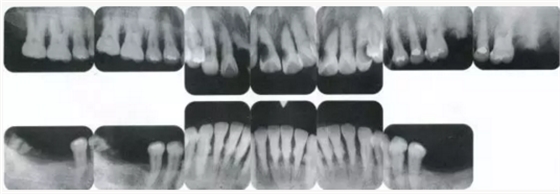

22222222222222222222222222.png

▲圖19-4

X光片。牙槽骨明顯缺失。